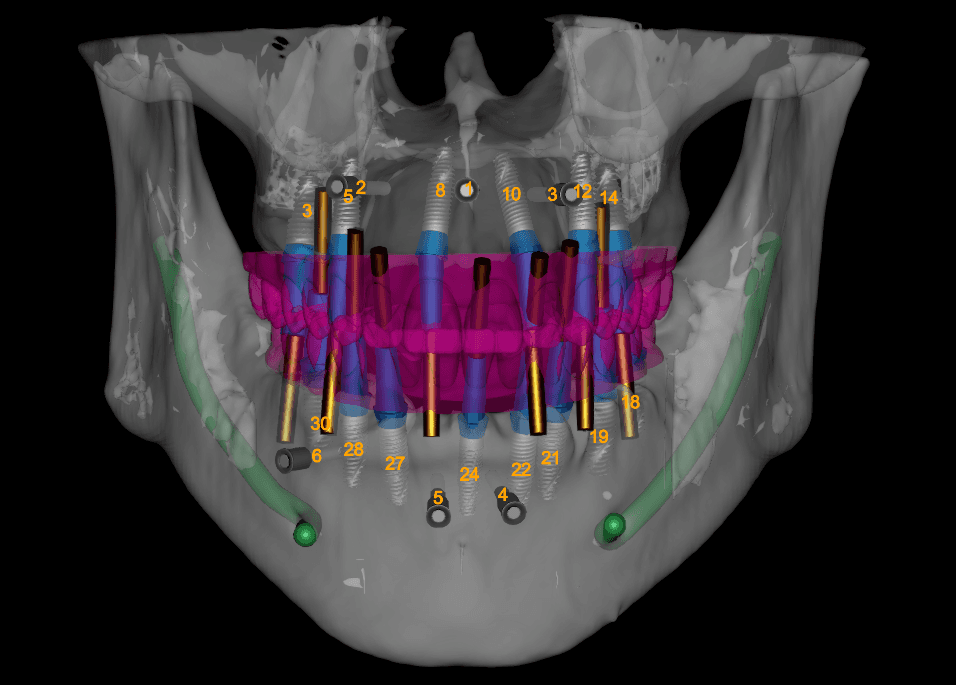

Elevate every implant case with 3Sixty’s AI-enhanced treatment planning led by experienced dentists and powered by a fully integrated digital workflow. From diagnosis to surgical guide design, we combine clinical insight with cutting-edge tech to ensure every detail is optimized for surgical precision and prosthetic success.

We merge CBCT scans, IOS files, and clinical records to create comprehensive, prosthetically guided plans. Every implant is positioned with anatomical awareness, surgical feasibility, and restorative intent from the outset.